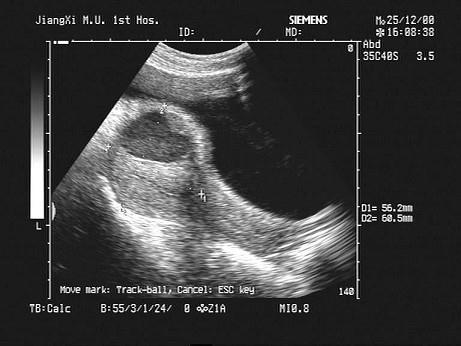

女性,44岁,取环术后下腹疼痛1天。B超检查如图,最可能的诊断为?(?)A.子宫血肿B.盆腔血肿C.子宫肌瘤D.子宫腺肌瘤E.肌瘤囊变

问题 女性,44岁,取环术后下腹疼痛1天。B超检查如图,最可能的诊断为?(?)

选项 A.子宫血肿 B.盆腔血肿 C.子宫肌瘤 D.子宫腺肌瘤 E.肌瘤囊变

答案 A